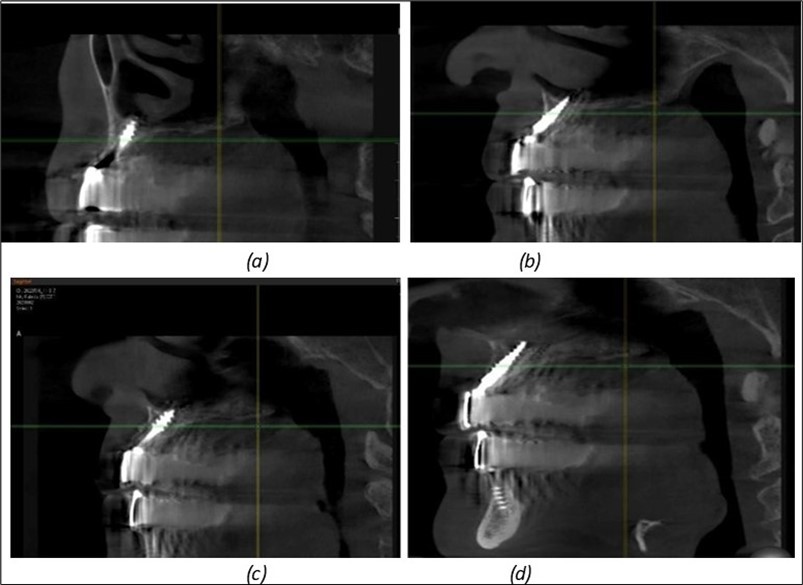

Figure 12.Implants fixed distally in quadrant 4 with fixation at the level of the mylohyoid line: (a) The most distal implant fixed in unaffected bone from the previous restoration; (b) The implant fixed in the area where the two stage implant was removed.

Figure 13.Corticobasal BCS implants fixed between the vestibular and lingual cortices with support on the basal bone: (a) BCS fixed between the lateral cortices; (b) BCS implant with support on the basal cortex.

Figure 14.Rx panoramic final situation control: (a) Panoramic X-ray with the addition of a distal BCS implant in quadrant 3 at 11.2022; (b) Control X-ray, 10.2023.